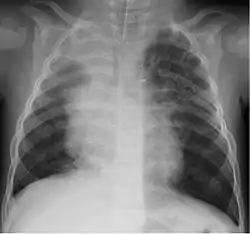

![]() Рентгенологічні ознаки пневмонії при ураженні 1-м бокавірусом людини у півторарічній дитини. Рентгенологічне затемнення (світле забарвлення рентгенограми) у верхній та середній частках правої легені. Рентгенологічні ознаки пневмонії при ураженні 1-м бокавірусом людини у півторарічній дитини. Рентгенологічне затемнення (світле забарвлення рентгенограми) у верхній та середній частках правої легені. | |